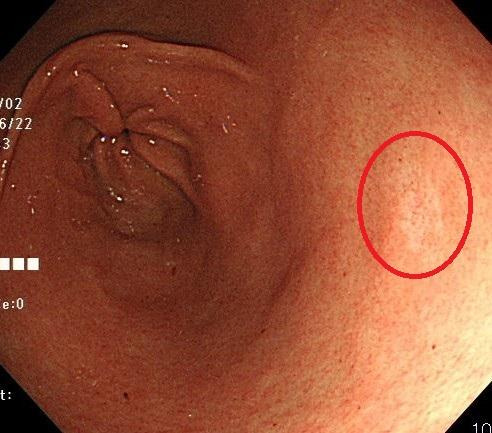

2. 내시경 중 조직 채취

의사는 내시경 카메라를 통해 위 내부를 관찰하면서 이상 부위를 발견하면, 내시경 끝에 부착된 작은 겸자(Forceps)를 이용해 점막의 일부를 매우 소량 떼어냅니다. 일반적으로 통증은 거의 없으며, 일부 환자는 ‘찌릿’한 느낌 정도만 느낄 수 있습니다. 한 번의 검사에서 2~5개 정도의 조직을 채취하는 것이 일반적입니다.